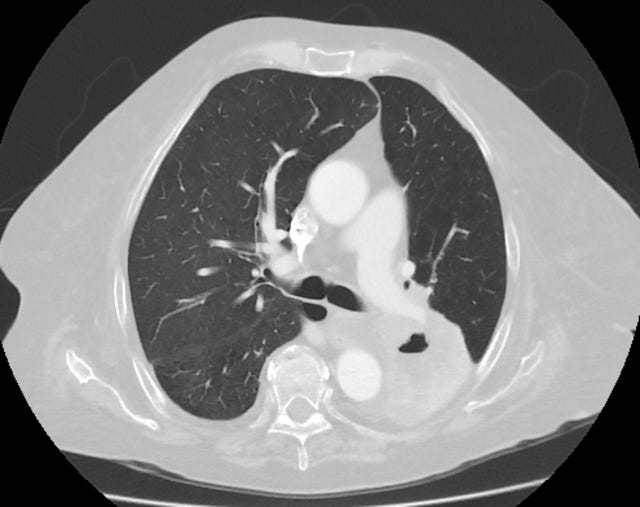

This one’s a bit harder, and most people at a glance won’t be able to tell what it is. Unsurprisingly, a radiologist could - they’d recognise it is a cross section of the lungs. They would tell you to imagine that the patient is lying on their back: you slice through their chest and look at the cross-section you’ve made. You’d see the backbone at the bottom, two large grey masses for the lungs and some ribs surrounding them. In this case, with the right knowledge, you’d also spot signs of disease: this image (apparently) shows “Cavitation of a lung squamous carcinoma, infrahilar, affecting the left lower lobe.”

The image is from a CT scan, which is a technique used to take pictures at 5 mm slices through the human body. They are hard to interpret because the angle is unfamiliar, and the bodily structures often look blobby and messy. A radiologist, of course, would have no trouble interpreting it and could give you chapter and verse about the patient and their health.